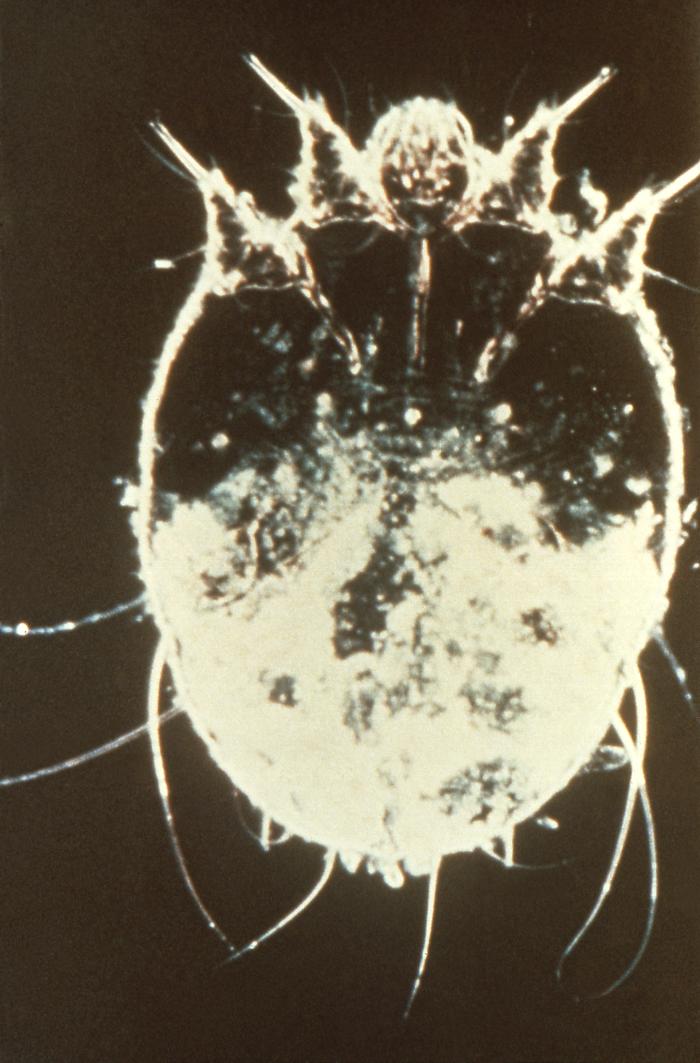

Sarcoptes scabiei es un ácaro pertenece al filo de los artrópodos, clase arácnidos y familia Sarcoptidae. Aunque las distintas variedades pueden infestar a diferentes mamíferos, la especificidad de huésped de cada variedad es fuerte, por lo que las infestaciones en humanos se deben a S. scabiei var. hominis (8).

Los adultos son microscópicos, con forma ovalada o redondeada y de color grisáceo. Las hembras miden entre 0,30-0,45 milímetros (mm) de largo y 0,25-0,35 mm de ancho. Los machos son más pequeños que las hembras. La larva que emerge de los huevos tiene sólo 3 pares de patas y al cabo de 3 o 4 días se transforma en ninfa que tiene 4 pares de patas; ambas formas son similares a los adultos pero más pequeñas. Los huevos son ovalados, con un tamaño de 0,10-0,15 mm.